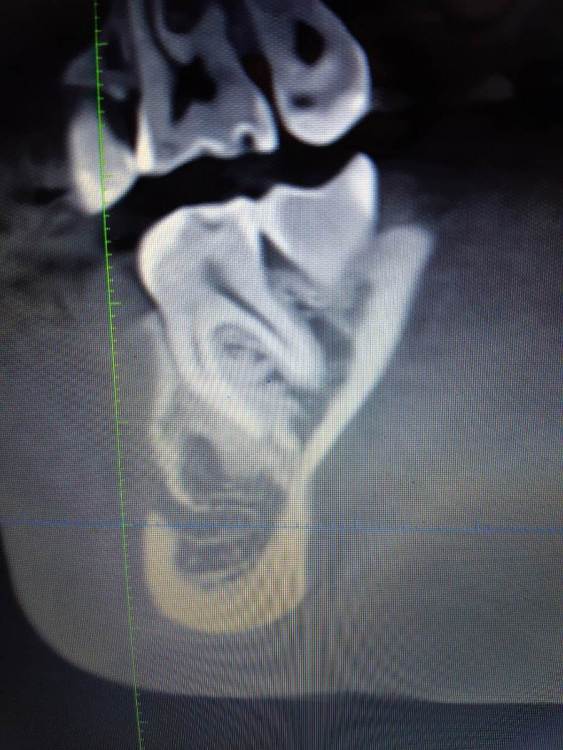

Доброго времени суток, коллеги! Кто может посмотреть КТ, делали по другому поводу, случайно найдено образование. Не беспокоило все это время. На оптг за 2019 год ничего такого не видно. Неужели придется удалять зуб вместе с образованием?

20210401_174112.jpg